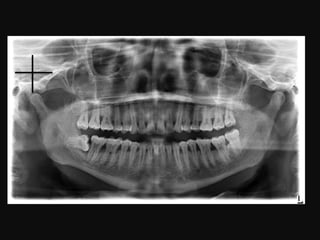

1. Mandibular condyle.

2. Neck of mandibular

condyle.

3. Coronoid process of mandible.

4. Ghost image, posterior aspect of

inferior border of left side of mandible.

5. Inferior alveolar (mandibular) canal.

6. Inferior border of mandible.

7. Superimposed shadow of

cervical vertebrae.

8. Mental foramen.

9. Submandibular fossa (lingual

salivary gland depression).

10. Mandibular angle.

11. External oblique ridge.

12. Sigmoid notch.

1. Mandibular condyle. 2.Neck of mandibular condyle. 3. Coronoid process of mandible. 4. Ghost image, posterior aspect of inferior border of left side of mandible. 5. Inferior alveolar (mandibular) canal. 6. Inferior border of mandible.

• 56.

7. Superimposed shadowof cervical vertebrae. 8. Mental foramen. 9. Submandibular fossa (lingual salivary gland depression). 10. Mandibular angle. 11. External oblique ridge. 12. Sigmoid notch.